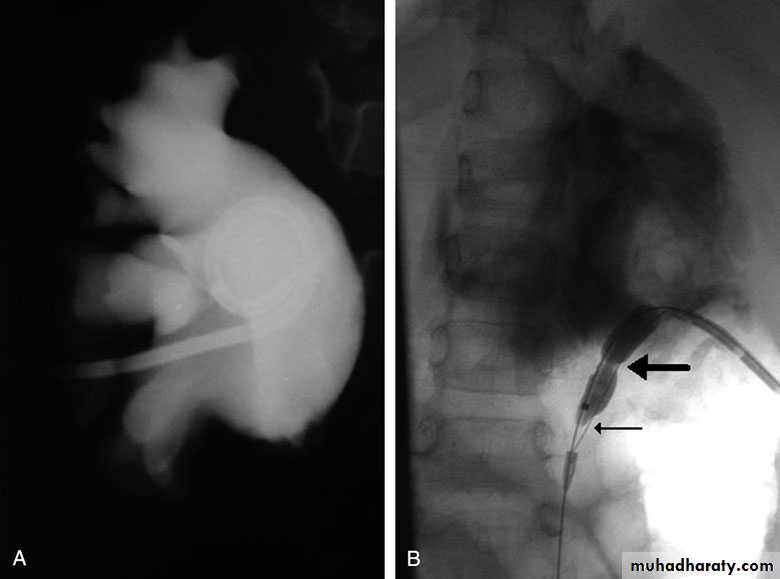

Postcaval (Retrocaval) ureter (Preureteral Vena Cava )

The right ureter pass behind the inferior vena cava

This might causes obstruction

Vascular abnormality

Incidence: about 1 in 1500

Although it is congenital, most patients present at 3rd or 4th decade.

Diagnosis: IVU

Treatment:

surgical correction involves ureteral division, with relocation and ureteroureteral or ureteropelvic reanastomosis,

usually with excision or bypass of the retrocaval segment, which can

be aperistaltic